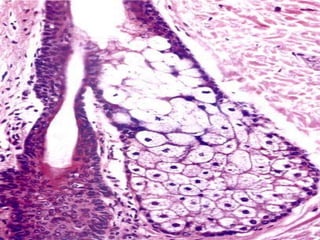

Structure of Hair Follicle

• Part of the epidermis that has been

invaginated into the dermis around the hair

root

• Its innermost layer continues with the surface

of the skin & outermost layer continues with

the dermis

• Found in dermis of the skin

• Ducts open into the hair follicle

• Holocrine gland

• Secretes sebumsebum: antifungal & anti bacterial.

Contains lipids & cholesterol

– Oily in nature

– Prevents dryness

– Resistant to moisture

• The secretary acinus has,

– flattened epithelial cells

– Centrally placed rounded cells / sebocytes